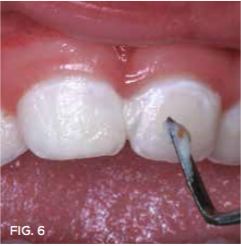

Case 2. This 2-year-old boy had mesial caries lesions of his maxillary central incisors associated with chronic plaque accumulation and lack of tooth brushing or flossing by the parents (Figure 5 and Figure 6). The parents, who were given extensive instructions to remedy the oral hygiene problem, consented to SDF application despite the black discoloration. They related that they not only wanted to avoid a repair appointment for the child, but they also liked the idea that traditional restoration could be delayed until he was older and could more easily tolerate treatment. Three months after initial SDF application, the solution was reapplied (Figure 7).

Fig 6. Much plaque accumulation; no oral home care apparent.

Fig 6